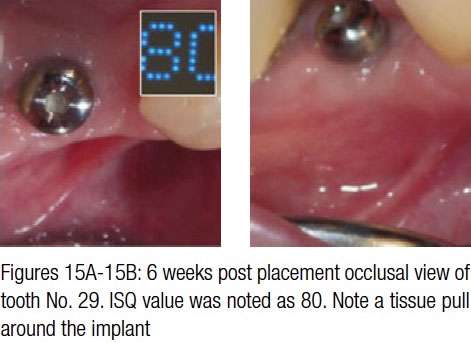

Case study 2

The 73-year-old female patient had a single implant on tooth No. 29 placed. Figures 15A and 15B show a noticeable buccal frenum pull present in the region. High mucogingival junction (evident in Figure 15B) indicates insufficient amount of keratinized attached gingiva. It was decided to perform a CO2 laser frenectomy/vestibuloplasty to increase the width of the attached gingiva. The laser procedure was performed utilizing the same laser settings and following the same protocol as previously described in Case study 1: